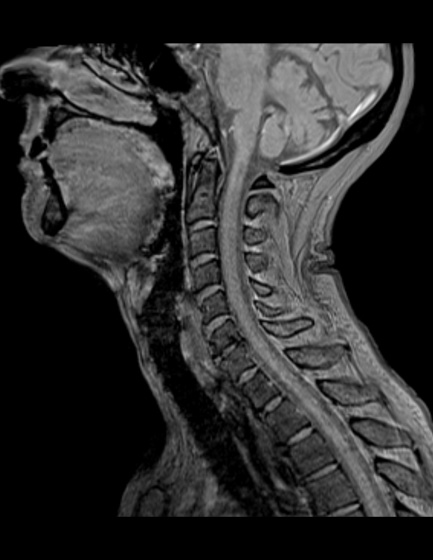

| 撮影可能な部位 | 頭部、脊椎、乳腺、腹部、骨盤部、関節など 全身領域 |

MRI検査依頼書(PDF)当院で撮影したMRI画像